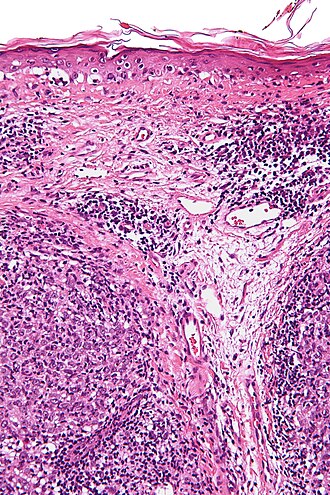

Lymphoepithelioma-like carcinoma. H&E stain.

LM clusters of cohesive squamoid cells with abundant dense cytoplasm, central nuclei +/- small/indistinct nucleoli, surrounded by a prominent lymphoid component

Features:

• Clusters of cohesive squamoid cells with:

• Abundant dense cytoplasm.

• Central nuclei +/- small/indistinct nucleoli.

• Surrounded by a prominent lymphoid component - key feature.